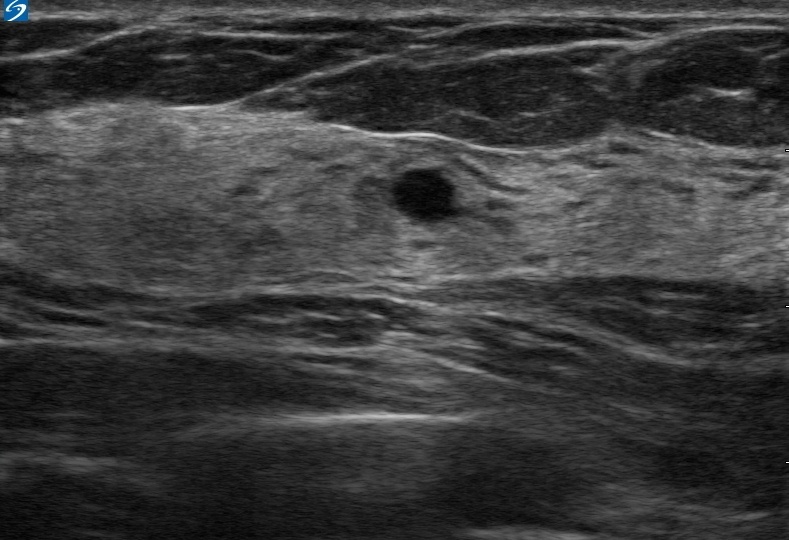

乳房囊肿图像